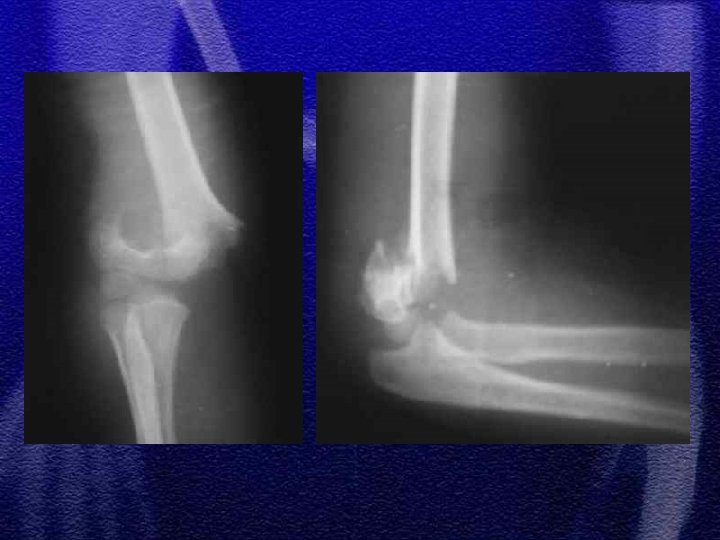

§ U dzieci występuje rzadko § Najczęściej powyżej 10 r. ż. § Często towarzyszy mu oderwanie nadkłykcia przyśrodkowego kości ramiennej, który może być przemieszczony do stawu § Rzadziej złamanie wyrostka dziobiastego kości ramiennej

§ Ustawienie przedramienia w nadmiernej koślawości powoduje nadmierne pociąganie i oderwanie nadkłykcia przez mięśnie zginacze przedramienia § Jest uszkodzeniem awulsyjnym § Często towarzyszy zwichnięciu stawu łokciowego § Leczenie złamania z przemieszczeniem operacyjne